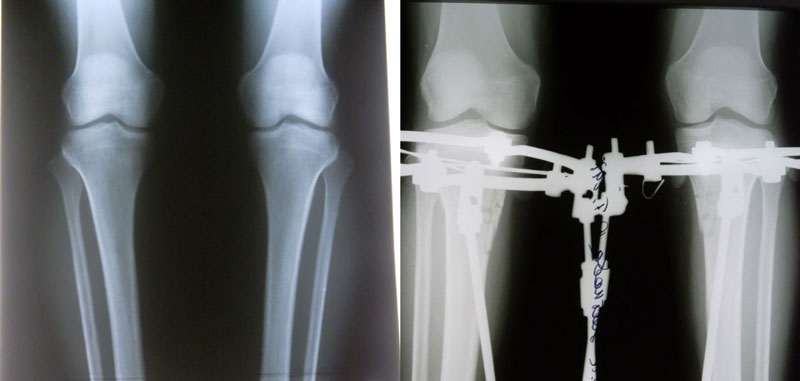

Я приехала 1 марта, сдала анализы, 2 марта ноги мои сломали) На следующий день Малиновка и Жасмин притащили ходунки и Жасмин так спокойно сказала-вставай...У меня аж все похолодело от страха, но встала..Все-таки нашатырь-классная вещь!!)))Постояла несколько секунд-и в койку...Трясло от слабости..Больновато, конечно, было, но терпимо,может уколы еще влияли..На след день сделала пару шагов сама, потом дошла до раковины..Ну, а когда поджало (имею в виду жуткое желание побыть в туалете одной